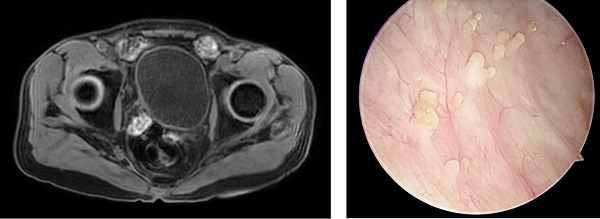

在順利完成3個(gè)周期的規(guī)范聯(lián)合治療后,2026年1月,復(fù)查的影像學(xué)檢查顯示,張先生原膀胱內(nèi)的巨大腫塊已經(jīng)基本消失,受侵犯的輸尿管管壁及周圍組織也得到修復(fù),右腎積水明顯減輕。

3.手術(shù)再評(píng)估。為了進(jìn)一步治療評(píng)估,團(tuán)隊(duì)對(duì)張先生原腫瘤部位及周圍組織進(jìn)行了充分切除。病理結(jié)果顯示已無癌細(xì)胞殘留。這意味著,綜合治療讓張先生體內(nèi)的腫瘤得到清除的同時(shí),膀胱功能也完整地保留了下來。經(jīng)泌尿腫瘤MDT團(tuán)隊(duì)討論,下一步還將繼續(xù)實(shí)施化療免疫“善后”,鞏固治療成果。

術(shù)后影像顯示腫瘤被切除